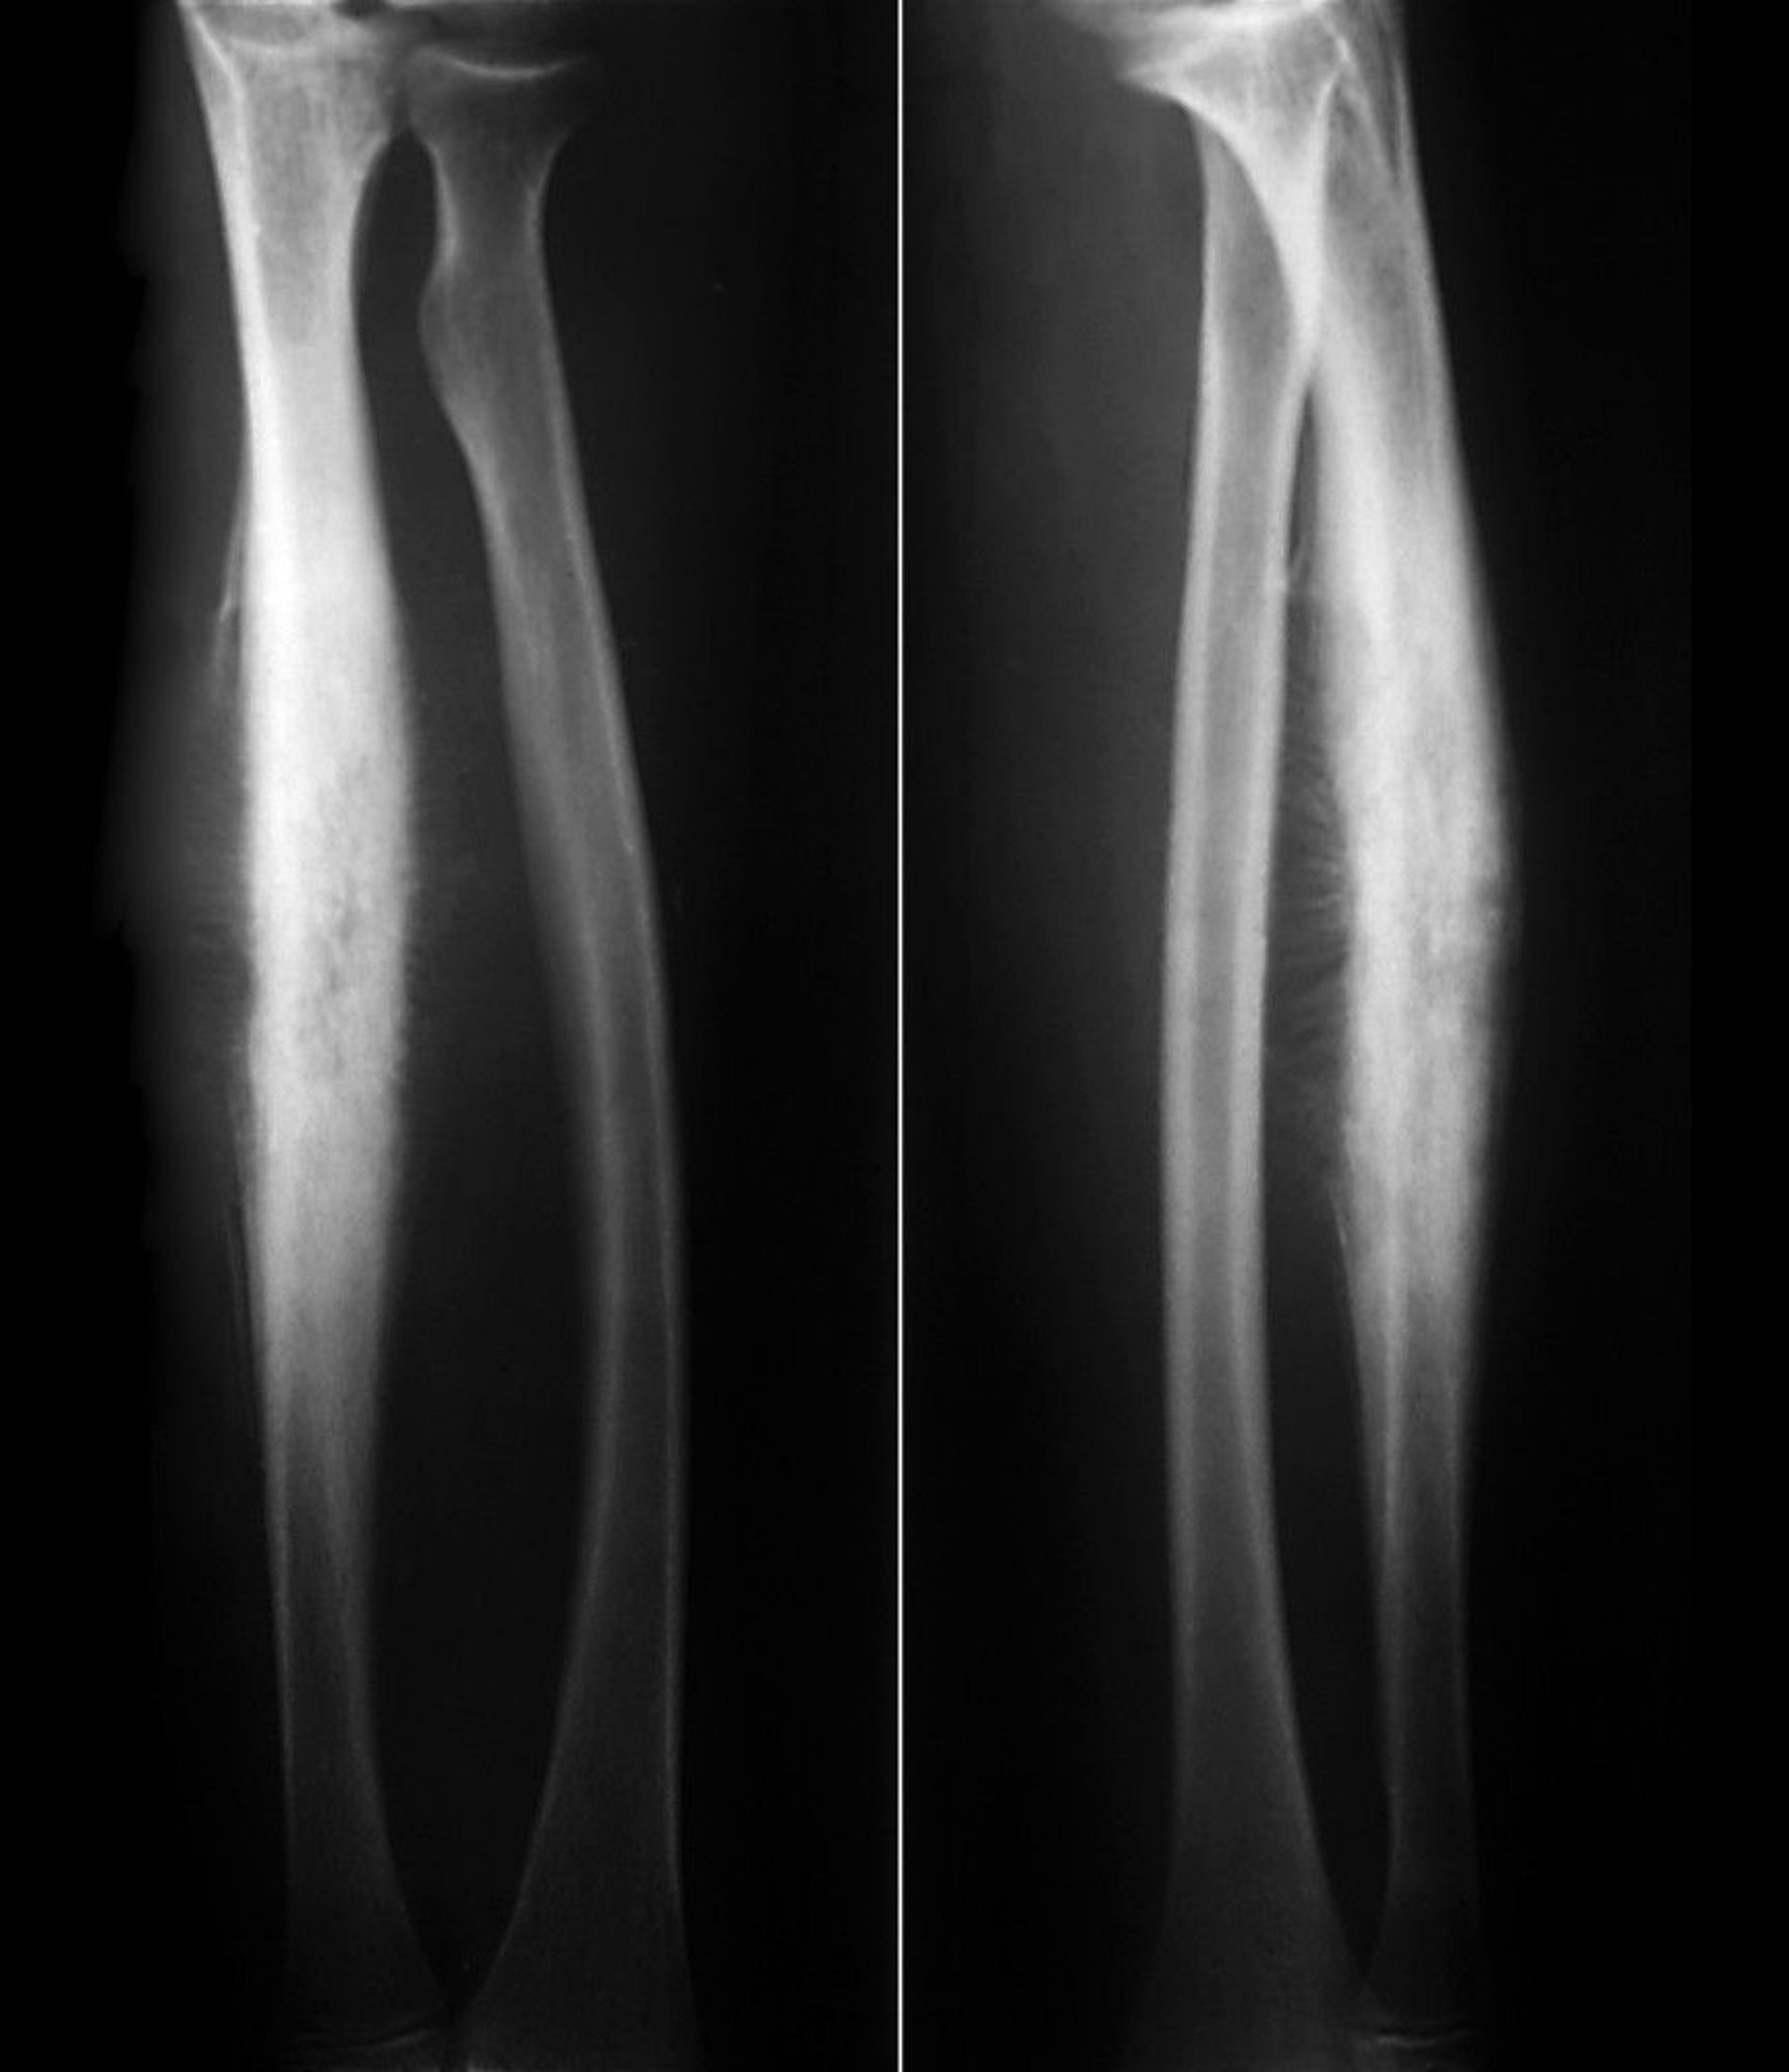

Ewing Sarcoma of the Radius

This Ewing sarcoma of the radial shaft shows subperiosteal reactive new bone formation in a classic "sunburst" periosteal reaction along with lytic destruction of cortical bone.